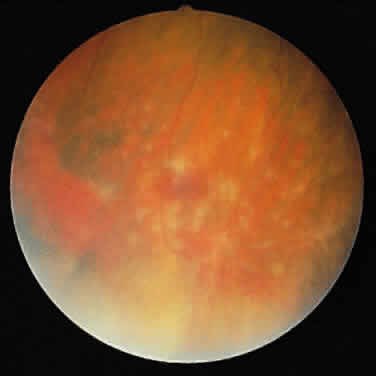

ARN is characterized by a retinal vasculitis affecting both the arteries and veins in the fundus, which is manifested by sheathing of the larger vessels (Fig. 2).7–10,16 Initially, patchy areas of peripheral retinal whitening (“thumbprint lesions”) representing full-thickness retinal necrosis are present or develop shortly after the vasculitis (Fig. 3). During a course that may span days or weeks, these patches coalesce into geographic areas (Fig. 4A). The entire peripheral retina (360 degrees) may be involved, or, more commonly, there are several noncontiguous patches of necrosis, each covering from a half to three clock hours (Figs. 5 and 6). The posterior segment lesions may not be detected without examination of the peripheral retina.

As the infection progresses, the leading edge of confluent retinal whitening advances toward the posterior pole (Fig. 7A). The retinitis may not progress posteriorly to the vascular arcades, sparing the macula and central vision. It is hypothesized that the retinal necrosis in ARN results from the combined effect of intracellular viral replication with subsequent cell death and vascular occlusion secondary to acute vasculitis. In some patients, the retinal vasculitic component may be much more prominent than the retinal necrosis.7 Optic disc swelling, either hyperemic or pallid, is a common feature of the ARN syndrome.1 Perivascular hemorrhages may be present (Fig. 8); however, widespread areas of retinal hemorrhage are atypical. Retinal vascular occlusion, often involving the arteries, can occur at any point during the clinical course. Without treatment, the inflammatory component of ARN typically burns out in 6 to 12 weeks, leaving behind a thin atrophic retina with associated pigmentary changes.10